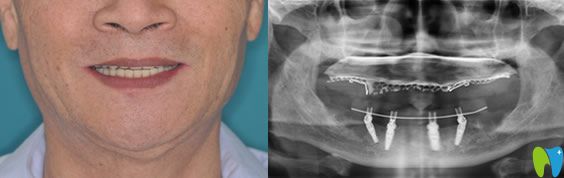

口腔情況:全口牙缺失;

種植方案:佛山智媄口腔醫(yī)生對林大爺?shù)目谇缓脱啦酃乔闆r進行了自信的分析,建議采用all-on-4全口種植技術(shù)。

All-on-4種植技術(shù):是歐美全新的種植牙技術(shù),也是非常適合半口及全口牙缺失的修復(fù)方法。僅需植入4顆人工牙根,就能將半口牙固定,一次完成,痛苦小,而且種植后的牙齒當(dāng)天就可以吃東西,能真正的做到即種即用。

林大爺做種植牙后感言:一直覺得像自己的情況需要種10幾顆牙呢,沒想到僅僅種了4顆種植體就“長出”了一排牙齒。而且在整個種植過程中沒有感覺到疼痛,醫(yī)生手法很輕,術(shù)后出血也很少,真的很意外我這么大年紀(jì)的人了,也恢復(fù)的很快,現(xiàn)在的牙齒可好用了,像年輕時的真牙一樣,終于能吃肉了!